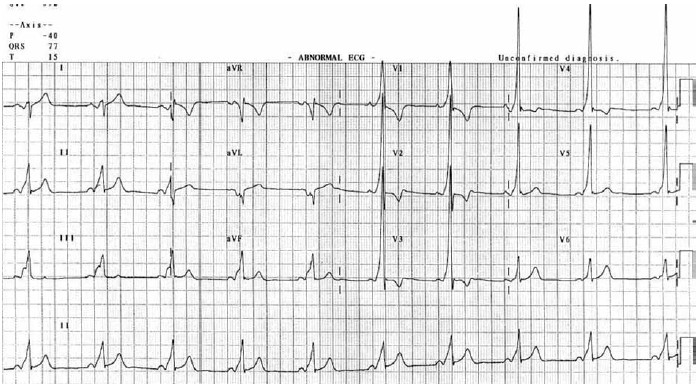

Homem, 20 anos, com queixa de palpitações, realiza o eletrocardiograma a seguir.

(Arquivo pessoal; imagem usada com autorização)

O eletrocardiograma indica